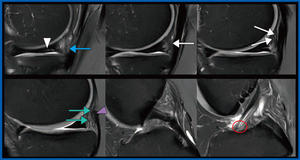

図1 AiCEによるdon’t touch regionの描出

骨軟部領域におけるDeep Learningを用いた高分解能イメージングの新たな展開

柿木 崇秀(京都大学医学部附属病院 放射線診断科)